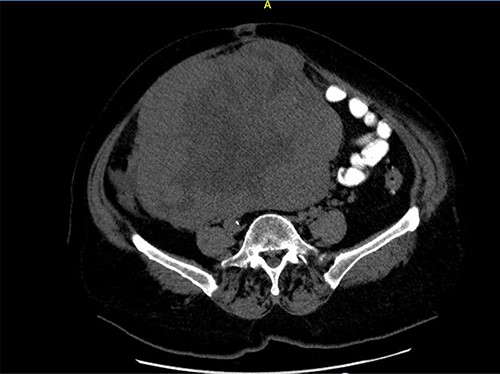

A 68-year-old female patient presented with a palpable abdominal mass in the lower parties of the abdomen. Three months earlier, she noticed painless abdominal distension and frequent urination. She underwent hysterectomy without oophorectomy for treatment of uterine myoma 12 years ago. The results of the transabdominal ultrasound and cross-sectional scan showed a 22 × 21-cm abdominopelvical mass, more right-sided, with both solid and cystic components, and incipient hepatomegaly with single hypodense lesion of liver, 8 mm in diameter. Blood test showed elevated serum cancer antigen 125 (CA 125) 185.9 U/ml, human epididymis secretory protein 4 (HE4) 228.3 pmol/l levels, and the risk of ovarian malignancy algorithm index (Roma index) was high with 79.9%. After a laparotomy, large tumorous mass 22 × 21 cm in diameter was found, which was grayish brown to yellowish color with nodular surface and cystic components, occupying the entire abdominopelvic cavity. (Figs 1 and 2) The tumor was well encapsulated and solid, fixated to the omentum and mesentery with large, nutritional, blood vessels and to surrounding tissue (Figs 3–5). Complete surgical resection of tumor, including bilateral adnexectomy, was performed. The post-operative period was uneventful. After 6 months of follow-up, magnetic resonance imaging of the abdomen and pelvis was performed, and there were no signs of tumor recurrence and serum levels of tumor markers were in reference ranges.

Close picture of axial CT scan of tumor, showing more right-sided localization.